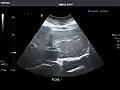

Right kidney

Kidneys: Right and left kidneys measure 11.5 cm and 12 cm in length respectively. No hydronephrosis. Small left lower pole kidney cyst.